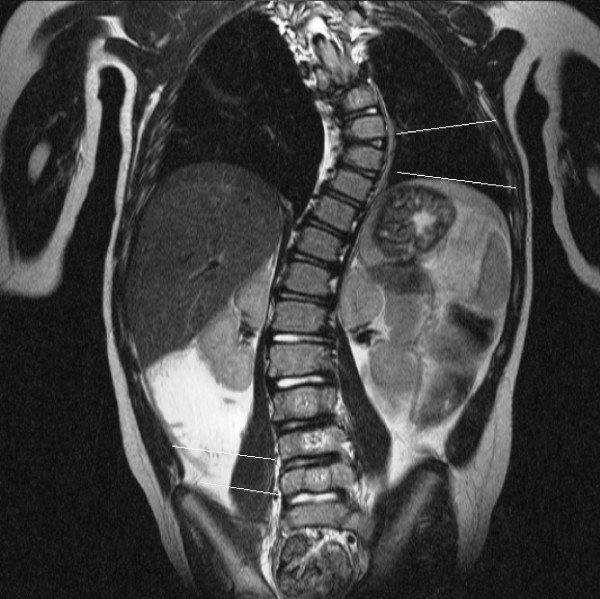

A dor é mais comum em adultos com escoliose, especialmente na escoliose degenerativa. Fatores que contribuem para a dor incluem:

● Degeneração discal: Desgaste dos discos intervertebrais pode causar dor lombar.

● Compressão neural: Curvaturas acentuadas podem comprimir raízes nervosas, levando a dor irradiada.